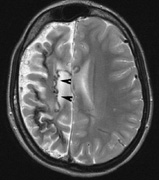

Intracranial leptomeningeal capillary vascular malformation (Figs. 21 and 22) is associated with seizures and contralateral neuromuscular weakness. Central nervous system involvement correlates highly with ipsilateral involvement of the V1 dermatome by a PWS.208,218

Fig. 22. Axial T2-weighted (a) and coronal T1-weighted (b) images of a 16-year-old boy with a port-wine lesion over the right side of his face. The right hemisphere is markedly atrophic and abnormal draining veins are seen within the right lateral ventricle (arrowheads). (c, d) The entire right hemisphere is covered by an enhancing pial angioma and the choroid plexi are enlarged. Enhancing retinal angiomas (arrows), typical of Sturge-Weber syndrome, are seen in (d).